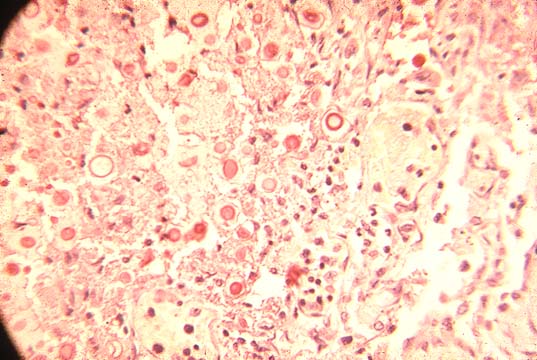

Salmonellosis

Fig.142-Salmonellosis

The illustration shows a granuloma produced by Salmonella typhi, the typhoid nodule, which consists of an intra parenchymal focus of necrosis with histiocytes, some neutrophils an will contain the gram negative organisms.